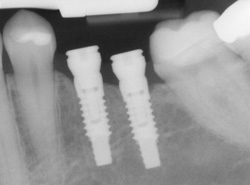

X-ray of an implant in position

implantsImplants are versatile. If you are only missing one tooth, one implant plus one replacement tooth will do the trick. If you are missing several teeth in a row, a few strategically placed implants can support a permanent bridge (a set of replacement teeth). Similarly, if you have lost all of your teeth, a full bridge or full denture can be permanently fixed in your mouth with a strategic number of implants.